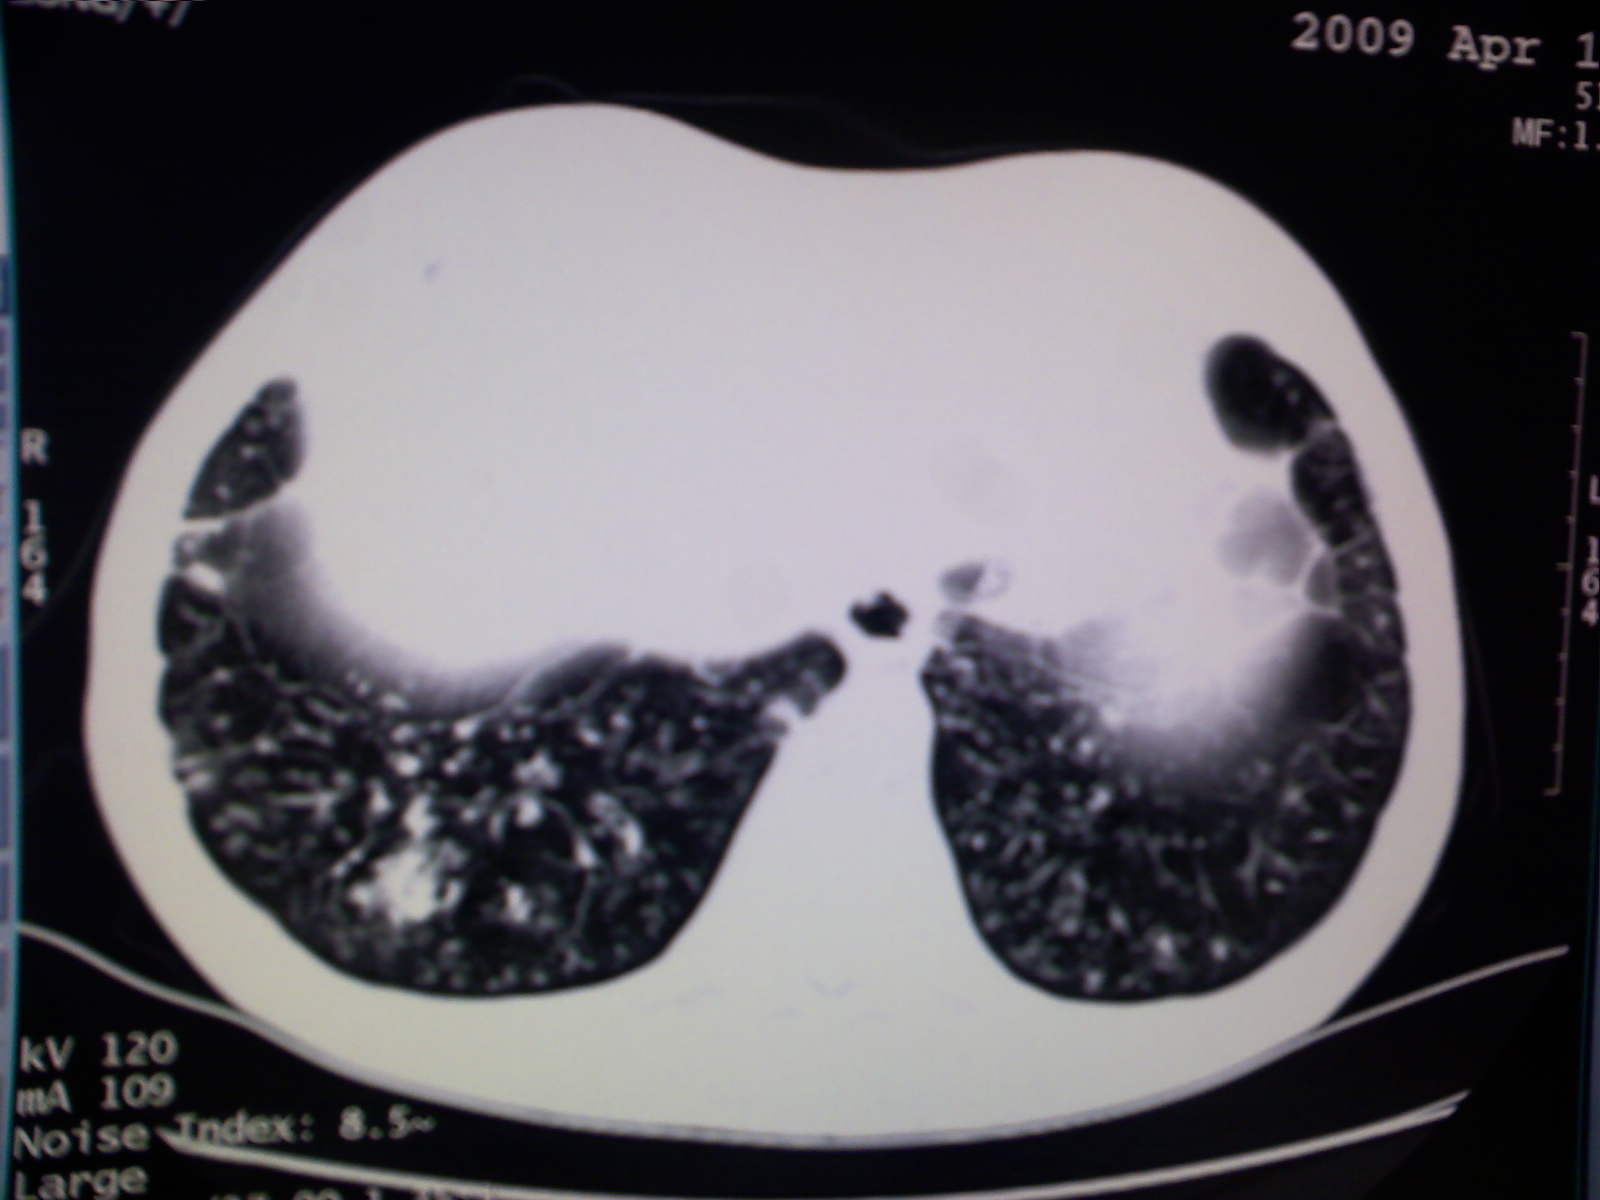

以下是引用卜一在2009-4-11 15:50:00的发言:[br]双肺继发性肺结核伴空洞形成,不排除合并霉菌感染!(病灶呈多形态 多特征 散在分布)。另:合并支气管扩张征伴感染!

以下是引用康鹏在2009-4-11 16:30:00的发言:[br]双肺继发性肺结核伴空洞形成合并感染[br]支气管扩张合并感染